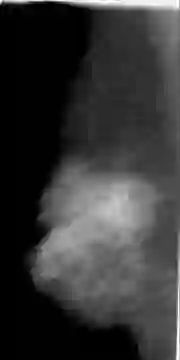

The deep learning technique has been shown to be effective in addressing several image analysis tasks within the computer-aided diagnosis scheme for mammography. The training of an efficacious deep learning model requires large amounts of data with sufficient diversity in terms of image style and quality. In particular, the diversity of image styles may be primarily attributed to the vendor factor. However, the collection of mammograms from large and diverse vendors is very expensive and sometimes impractical. Motivatedly, a novel contrastive learning method is developed to equip the deep learning models with better generalization capability. Specifically, the multi-style and multi-view unsupervised self-learning scheme is carried out to seek robust feature embedding against various vendor styles as a pre-trained model. Afterward, the pre-trained network is further fine-tuned to the downstream tasks, e.g., mass detection, matching, BI-RADS rating, and breast density classification. The proposed method has been extensively and rigorously evaluated with mammograms from various vendor-style domains and several public datasets. The experimental results suggest that the proposed domain generalization method can effectively improve the performance of four mammographic image tasks on data from either seen or unseen domains and outperform many state-of-the-art (SOTA) generalization methods.